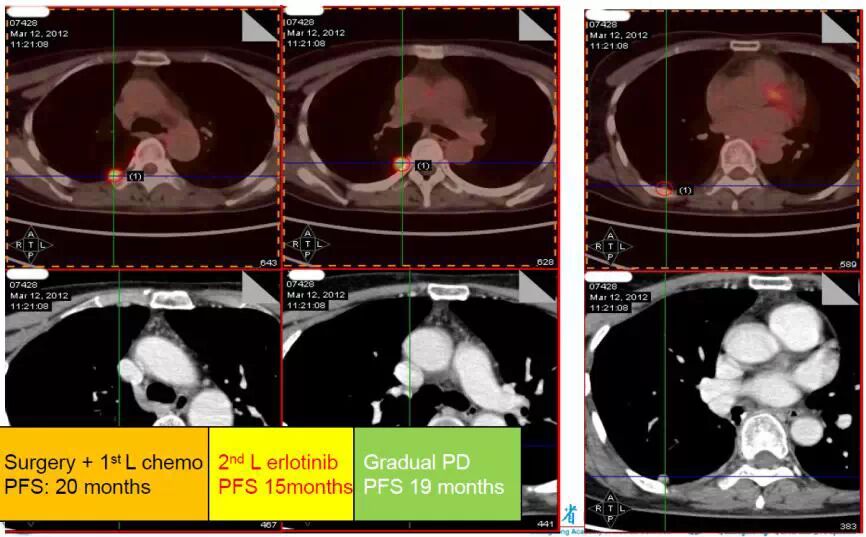

图3. 手术+一线化疗的PFS为20个月、二线EGFR-TKI治疗PFS 为15个月、缓慢进展后PFS为19个月

患者继续口服厄洛替尼至2012年3月,大部分病灶稳定,但是PET-CT显示其中一个病灶增大:直径1.4cm、SUVmax 8.2, CEA 58.49ng/ml。